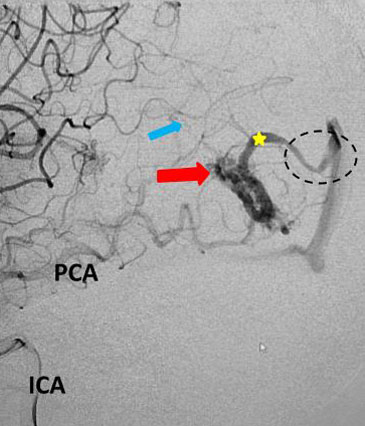

Fig 3. Lateral view, late-arterial phase of a right internal carotid artery (ICA) injection. Filling of the AMV (red arrow) by the fetal posterior cerebral artery (PCA) and small middle cerebral artery feeder (blue arrow). The large tortuous draining vein (yellow star) with venous stenosis and the suggestion of clot (dotted circle) can be seen.